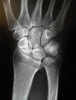

손목에서 상당한 척골 양성 변이(positive ulnar variance)가 관찰됩니다(7mm 이상의 척골 양성 변이 : 골간막의 완전 파열과 요골의 근위 전위를 의미).

X-ray : 전완부 골간막 손상(Essex-Lopresti injury)